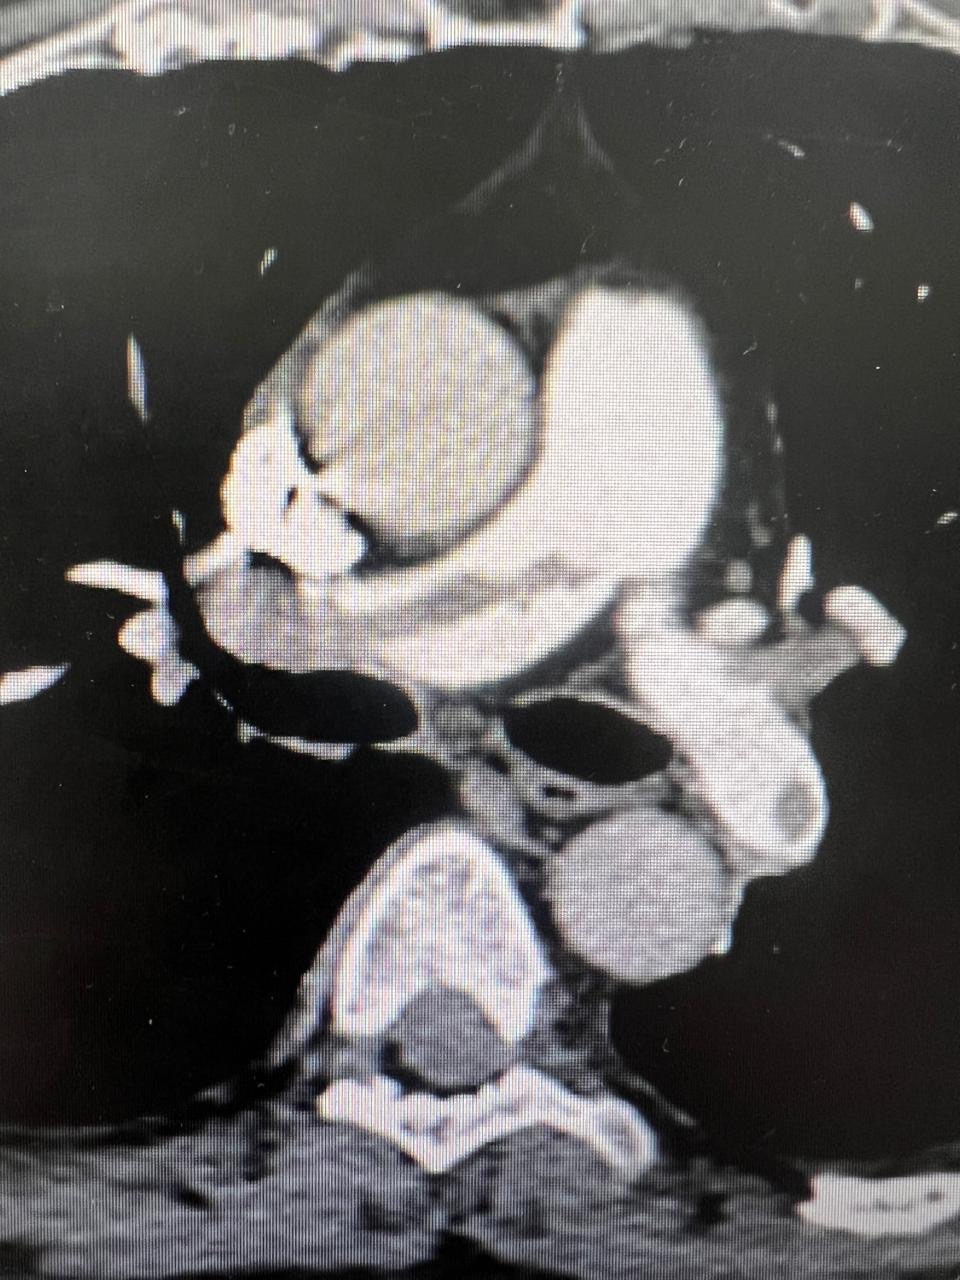

All patients were submitted to a preoperative pulmonary CT-SCAN, showing a large thrombus burden at main pulmonary arteries (figures 3 and 4).

Figure 3: CT-Scan demonstrating large thrombus burden at left pulmonary artery

Figure 4: CT-Scan demonstrating large thrombus burden at righ and left pulmonary artery